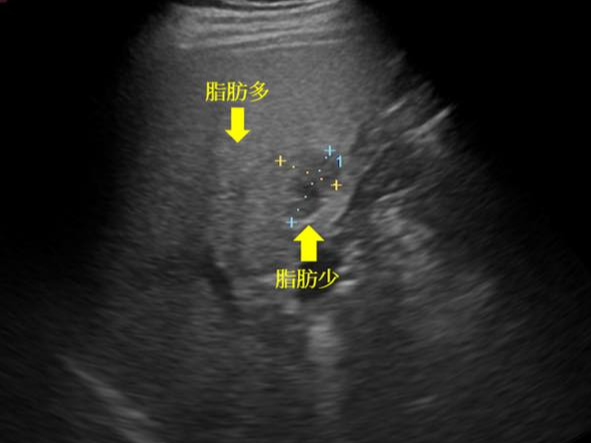

- 공기나 뼈로 가려진 장기(예: 위, 장 등)는 시야 확보 어려움

- 지나치게 비만하거나 복부 지방이 많은 경우 해상도 저하